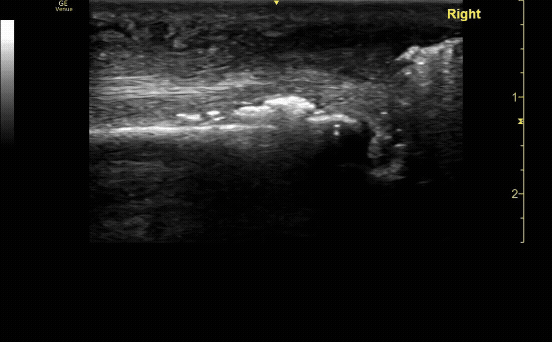

Ring Down Artifact: appears as a continuous, bright vertical echo extending deep to a gas bubble, caused by resonance of trapped air. Air in necrotizing fasciitis (seen here) or bowel gas can also lead to bright lines extending deep, obscuring any structures below.

c/o Adam Roussas, MD